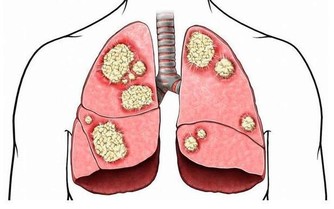

原因三,腸易激綜合徵

為什麼一喝冷水一吃辣就拉肚子

這是一種胃腸道疾病,腸道很容易因為刺激而發生多種不適,一般表現腸道激動→腹痛、腹部不適→排便。另外,還可能伴有腸鳴、腹瀉、放屁、腸道痙攣等多種問題。

飲食上如果吃了冷的、辣的便會發生,一般腹瀉1-2次,便會好轉。除了飲食因素,精神因素,如焦慮、抑鬱都可能導致。這些甚至在喝酒、吃太燙食物之後,也可能發生腹瀉。